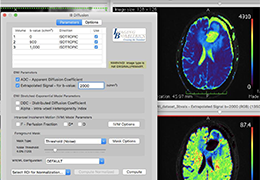

人工智能不再是一项抽象的承诺。Eclipse 引擎为 ImageView 软件提供支持,将 AI 付诸于无可争议的行动,即通过成像智能、工作流智能和分析智能推动产生具体、可衡量的结果。

Eclipse 成像智能功能提供强大的处理能力和最佳质量的影像,同时减少质量错误并提高剂量效率。

凭借 AI、专有算法和先进的影像处理能力,提供出色的影像质量和无与伦比的诊断信心。

体验 Eclipse 图像处理